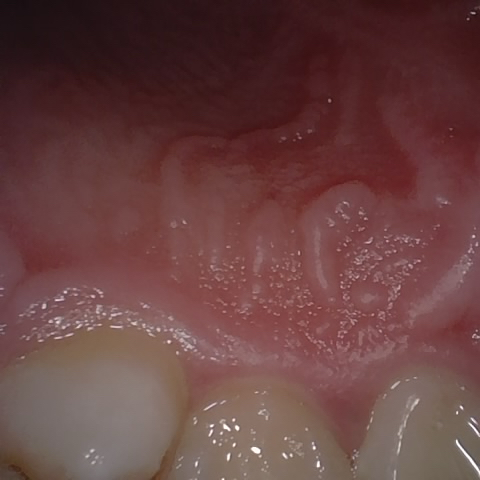

NHD39990

Annotated as "Good"